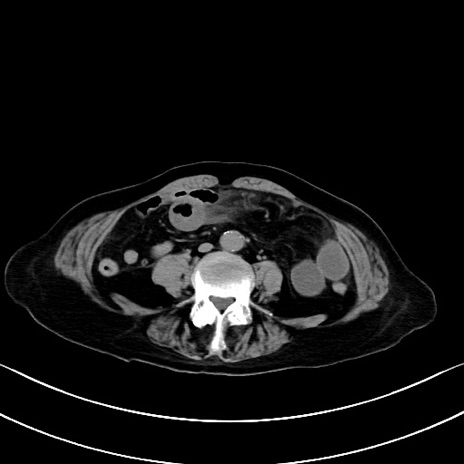

横断像

他院CT